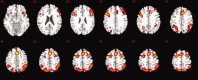

Gender differences have been well established in verbal and spatial abilities but few studies have examined if these differences also extend into the domain of working memory in terms of behavioural differences and brain activation. The conclusions that can be drawn from these studies are not clear cut but suggest that even though gender differences might not be apparent from behavioural measures, the underlying neural substrate associated with working memory might be different in men and women. Previous research suggests activation in a network of frontal and parietal regions during working memory tasks. This study aimed to investigate gender differences in patterns of brain activation during a verbal version of the N-back working memory task, which incorporates the effects of increased demands on working memory. A total of 50 healthy subjects, aged 18 to 58 years, that were equally split by gender were recruited matched for age, levels of education and ethnicity. All subjects underwent functional magnetic resonance imaging. We found that men and women performed equally well in terms of accuracy and response times, while using similar brain regions to the same degree. Our observations indicate that verbal working memory is not affected by gender at the behavioural or neural level, and support the findings of a recent meta-analysis by Hyde ([ 2005]: Sex Roles 53:717-725) that gender differences are generally smaller than intra-gender differences in many cognitive domains.